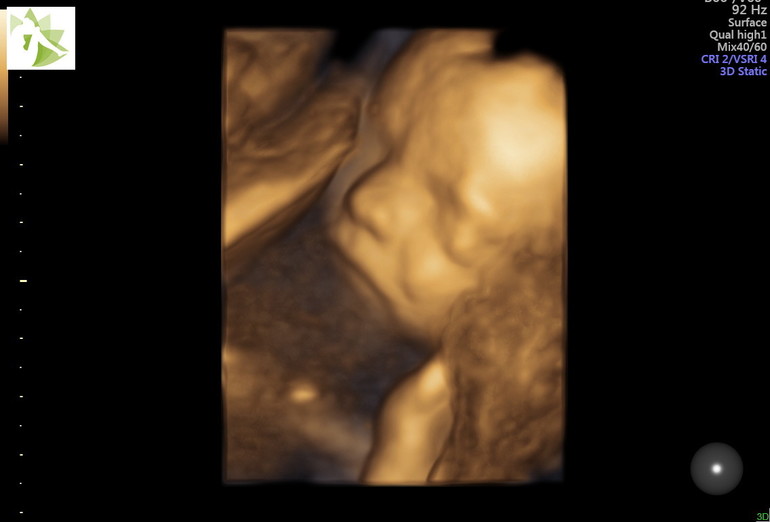

На малышке надеюсь не отразилось, по крайней мере результаты скрининга всё в порядке, растём и весим 500 грамм.